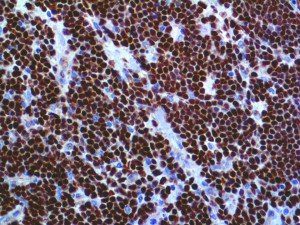

It is the ICU physician who is most likely to witness one of the deadliest manifestations of the abnormal immunological response, the cytokine storm syndrome (CSS). This response is also referred to by some as the cytokine release syndrome (CRS). CSS is characterized by continuous activation and expansion of macrophage and lymphocyte populations, which secrete large amounts of cytokines, causing the cytokine storm. This massive cytokine release is akin to hemophagocytic lymphohistiocytosis (HLH) disease, a syndrome characterized by initial unchecked and persistent activation of cytotoxic T lymphocytes and NK cells.

Clinical and laboratory manifestations of HLH include fever, enlarged liver and/or spleen, neurologic dysfunction, coagulopathy, liver dysfunction, cytopenias (i.e., low levels of erythrocytes, leukocytes, and/or platelets), hypertriglyceridemia, hyperferritinemia, hemophagocytosis, and eventually diminished NK cell activity as the immune system becomes progressively paralyzed. HLH can be familial (primary HLH) or secondary to another disease process (sHLH), such as rheumatic disease, in which it is referred to as macrophage activation syndrome (MAS, characterized by elevated ferritin).